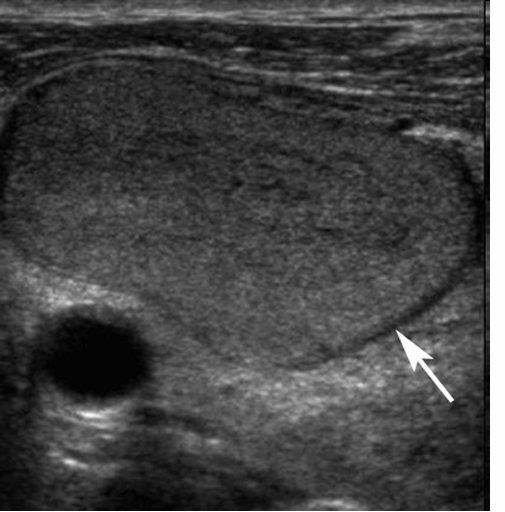

ultrasonography (US)

US features of nodules- benign, maligant

-halo sign

-microcalcifications

-increased vascularity